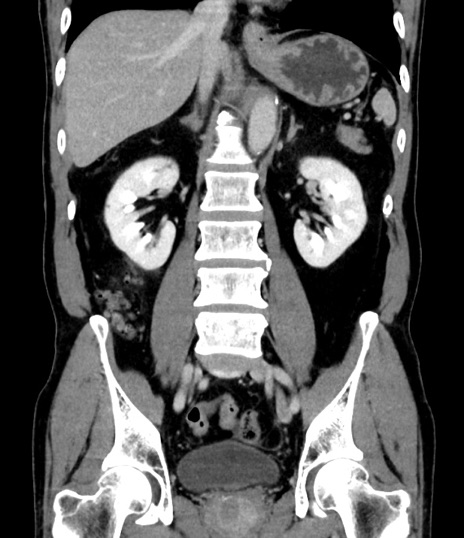

症例8(冠状断像)

【症例】 60歳代男性

【主訴】 黒色吐物

【現病歴】 4日前から嘔気自覚、2日前の朝食後にも嘔気あり、自分で手で嘔吐反射起こし嘔吐したところ血が混ざっていたため受診。

【既往歴】 5年前汎発性腹膜炎を伴う急性虫垂炎で手術、高血圧、前立腺肥大症、高脂血症

【身体所見】 腹部正中に手術癩痕あり 腹部平坦・軟圧痛なし膨満感あり

【データ】WBC 8400、CRP 4.54